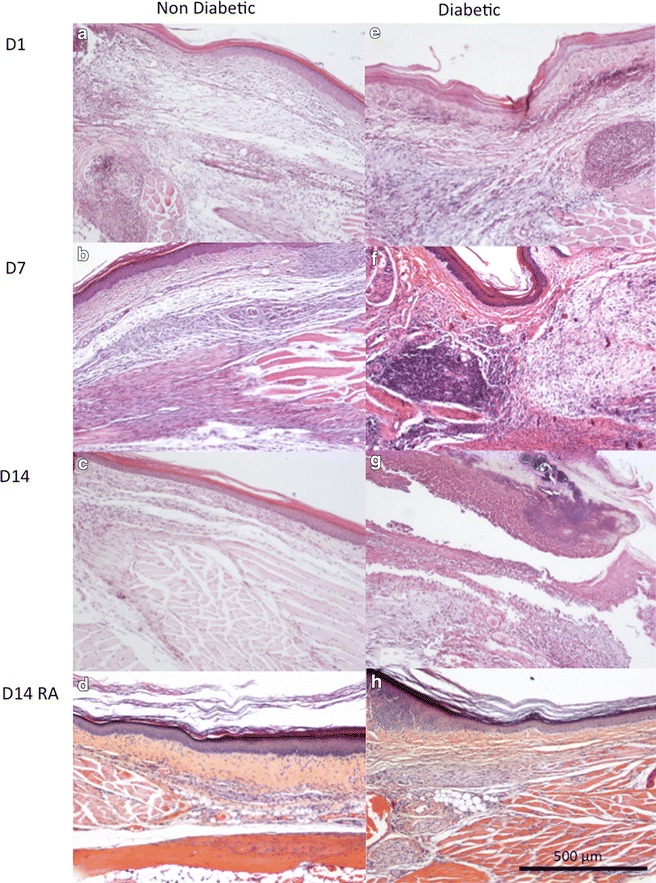

Histology of mice paws

Histology of hind paws is shown in Figure 4. Wound healing occurred in non-diabetic mice paws between D1 and D14 (compare Figure 4a–c) whereas persistent acute inflammatory cells with delayed wound healing were observed in diabetic mice paws at D14 (Figure 4e–g). RA did not alter healing in non-diabetic mice at D14 (Figure 4d) whereas it reduced inflammation and improved wound healing in diabetic mice paws (Figure 4h).

Figure 4.

Histology of mouse hindpaws. The effect of levobupivacaine and sufentanil were tested on histopathology of diabetic and non-diabetic mouse hind paws at different days postsurgery: a non-diabetic mice 1 day (D1) after skin incision showing acute inflammatory infiltration with polynuclear cells and oedema. b Non-diabetic mice 7 days (D7) after skin incision showing myofibroblastic proliferation with some lymphocyte inflammatory cells. c Non-diabetic mice 14 days (D14) after skin incision showing wound healing of the conjunctive tissue with only few inflammatory cells and still fibroblastic superficial proliferation. d Non-diabetic mice with RA at D14 showing wound healing of the conjunctive tissue with only few inflammatory cells and still fibroblastic superficial proliferation. e Diabetic mice at D1 showing acute inflammatory infiltration with polynuclear cells and oedema. f Diabetic mice at D7 showing persistent acute inflammatory cells and oedema. g Diabetic mice at D14 showing persistent acute inflammatory cells and oedema. h Diabetic mice with regional anaesthesia at D14 showing wound healing of the conjunctive tissue with only few inflammatory cells and still fibroblastic superficial proliferation.

Wound healing of the incised paw, observed as secondary parameter, appeared improved by RA in the diabetic mice. RA has been reported to impact local inflammation and wound healing with either neutral, negative or positive effects on healing in non-diabetic animals [52]. Normal wound healing consists of haemostasis, inflammation, proliferative phase and fibrotic remodelling. In our study neutrophils infiltration and oedema were similar in diabetic and non-diabetic mice paws at D1 post-surgery. At D7, lymphocyte/plasmocytes/fibroblasts replaced neutrophils in non-diabetic mice whereas neutrophils were still present in diabetic mice. At D14, fibrosis (remodelling with fibroblasts) was observed in non-diabetic mice whereas an inflammatory state was still observed in diabetic mice paws. When RA was performed, no alteration was observed in non-diabetic mice at D14 (remodelling) whereas remodelling was induced in diabetic mice. Bupivacaine has been reported to influence cutaneous wound inflammation (increased neutrophil numbers) in mice while healing (re-epithelialization) was not impaired [53]. In rats, levobupivacaine augmented the fibrotic remodelling [54]. However, despite early beneficial effects, long time levobupivacaine impaired wound healing in rats [52]. Our preliminary histopathological observation is compatible with a positive impact of RA on healing in the diabetic animals (Figures 4, 5).